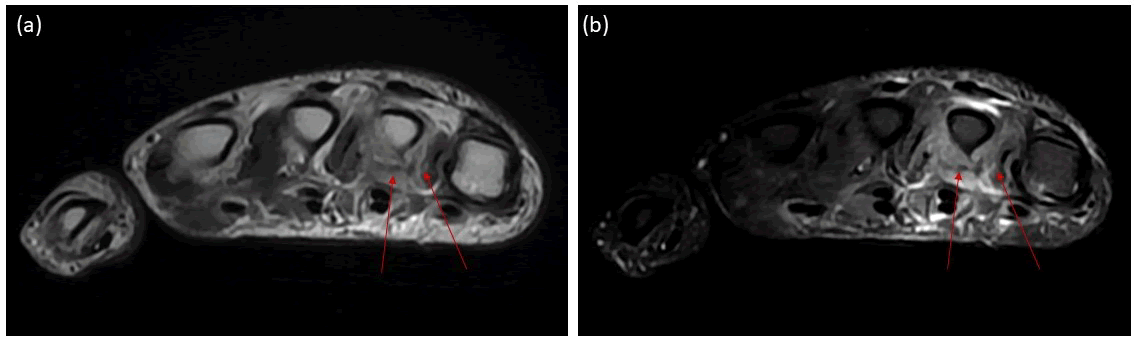

The patient underwent a hand MRI, which revealed denervation edema in the third and fourth lumbrical muscles (Figure 1). Ulnar nerve neuropathy was considered, prompting a wrist MRI to assess Guyon’s canal.

Figure 1. a) Hand MRI, axial T2 and b) T2 fat saturation sequence demonstrate atrophy and edematous signal in the third and fourth lumbrical muscles (arrows).